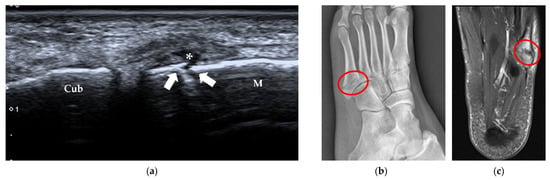

| Stress fracture | 2nd and 3rd metatarsals | periosteal lifting or cortical disruption, hypoechoic hematoma above the cortical bone |